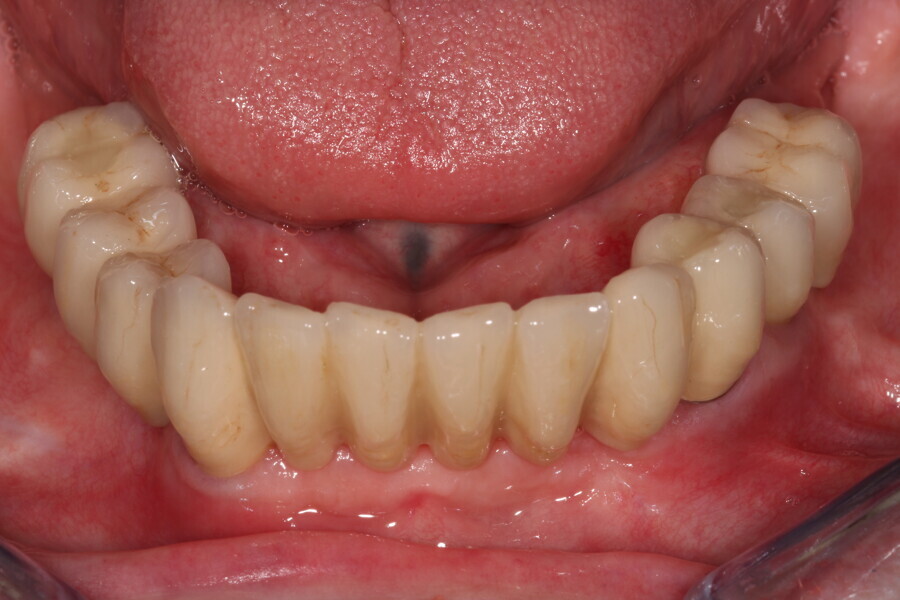

Fig. 17: Finished screw-retained bridge in situ.